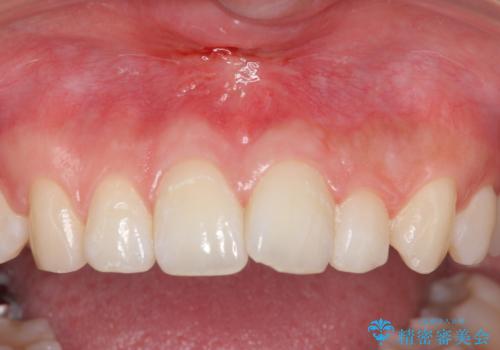

上唇小帯切除

矯正をする時、上唇小帯が残っているときれいに前歯が並ばない事があり、

矯正ができても上唇小帯のせいで前歯が後戻りする原因にもなります。

また、上唇小帯が長くて歯が磨きにくく、う蝕や歯周病の原因にもなります。